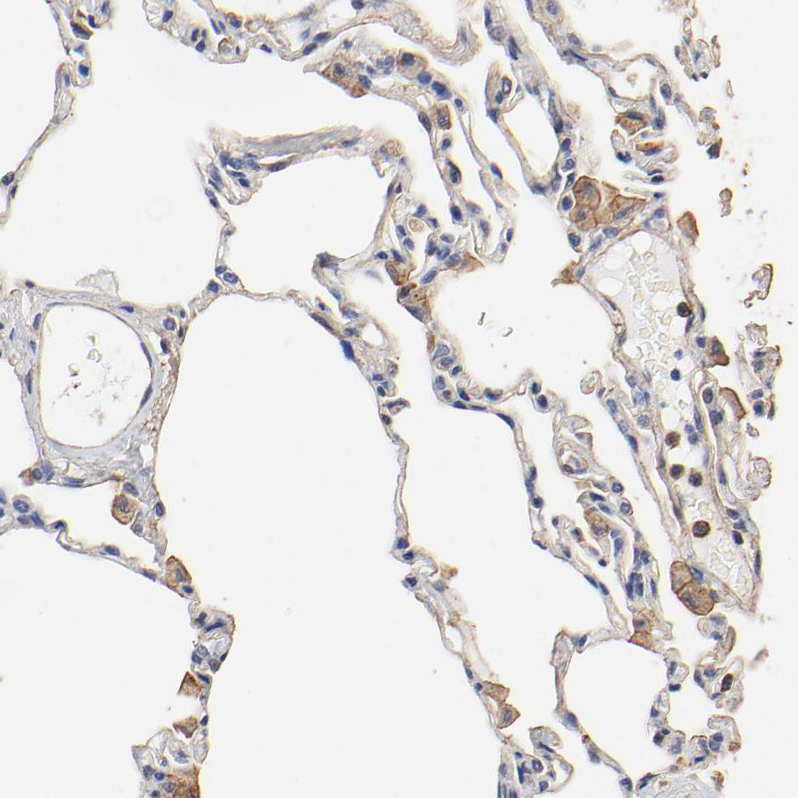

Immunohistochemical staining of human lung shows moderate cytoplasmic positivity in macrophages.